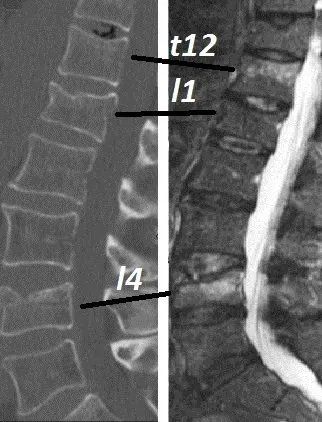

Generalmente le sollecitazioni che apportano un maggior effetto sul rachide in ortostasi sono rappresentate dalla forza di compressione, che è costante, e la forza flessoria che invece è variabile e che dipende dal momento flettente. Conoscere l’entità della cifosi contribuisce a comprendere l’intensità del movimento flessorio.